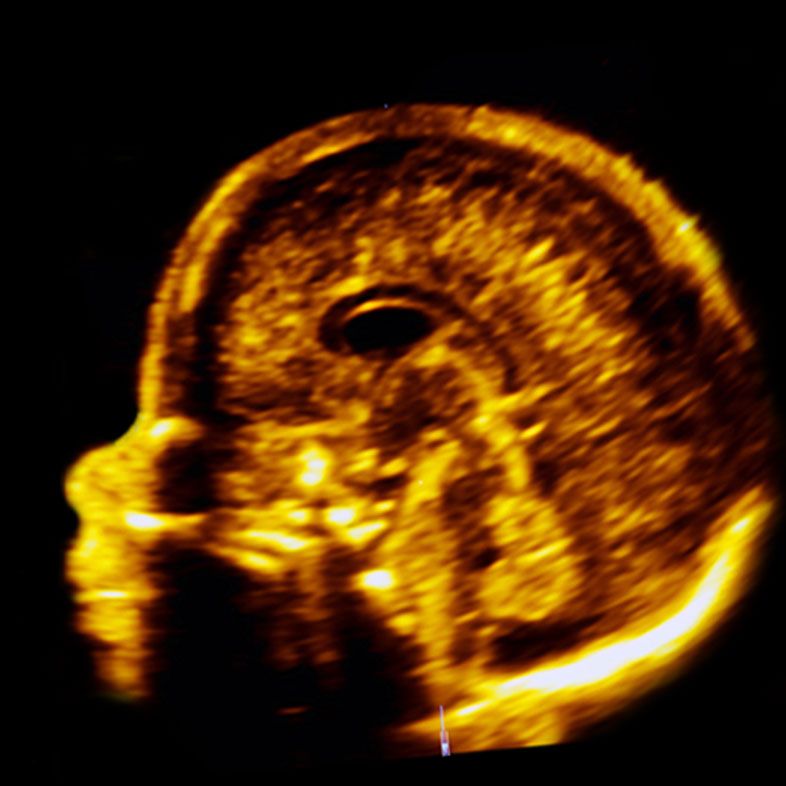

Your baby’s brain at 20 weeks – we are experts in Neurosonography

By 20-22 weeks of pregnancy, you are roughly halfway through your journey. This is an ideal time to re-examine the anatomical development of your baby using the Anomaly Scan. More specifically, we recommend the London Pregnancy Clinic Scan to be performed at 22 weeks, when the major structures of the baby’s brain are completely developed.

The Anomaly Scan involves a thorough examination of the fetal anatomy including a top-to-toe examination of the baby and its environment in the womb. We have the most comprehensive list of organs and structures that we examine, paying special attention to the fetal brain and heart.

- Our Anomaly Scan is scheduled at a slightly later gestational age (preferable 21-22 weeks) because some important structures of the brain are not completely developed at 19 weeks, which is when the majority of the NHS scans are performed,

We check the corpus callosum, an important midline structure of the brain, which is challenging to examine,

We have the latest 3D/4D technology available to our clinicians (quality of image depends on general resolution of the scan and can sometimes be low before 25-26 weeks)